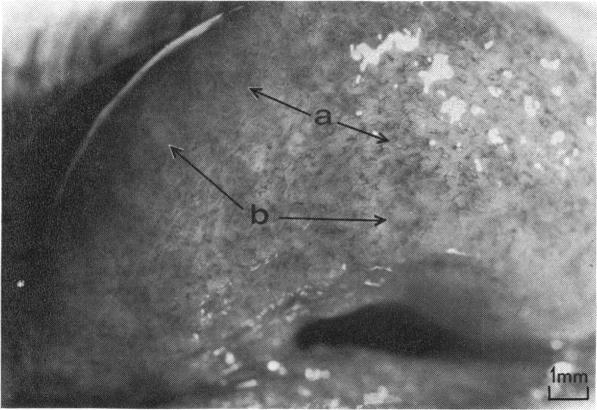

Since July 1973 cases of keratoconjunctivitis resembling epidemic keratoconjunctivitis were observed in the External Eye Disease Clinic at Moorfields Eye Hospital; City Road, London. Adenovirus type 19 was isolated in human embryonic kidney cells from 21 patients. The majority were males between 20 and 40 years old. A small hospital outbreak involving six patients occurred. Clinical features of the disease, consisting of moderate to severe follicular conjunctivitis, major subepithelial punctate keratitis, sometimes with pseudomembrane and scarring, were closely similar to those of epidemic keratoconjunctivitis caused by adenovirus type 8. This similarity, as well as the ability of the agent to cause hospital outbreaks, indicates that adenovirus type 19 is a cause of epidemic keratoconjunctivitis. A case of bilateral chronic papillary conjunctivitis that persisted for 16 months following an acute onset was described. Adeno 19 was isolated from the eye of the patient after 12 months of recrudescent or recurrent illness. Chronic adenovirus infection lacking the usual clinical picture of an acute follicular reaction has not hitherto been described. Such cases are probably important because of the obvious danger of continuing the carriage and shedding of infective adeno 19 from one outbreak to another, by presenting subsequently in eye clinics, and providing an unrecognised source of infection to initiate further outbreaks of hospital transmission.

自1973年7月起,伦敦市路摩尔菲尔德眼科医院的外眼病诊所观察到了类似流行性角结膜炎的角膜结膜炎病例。从21名患者的人胚肾细胞中分离出了19型腺病毒。大多数患者为20至40岁的男性。发生了一起涉及6名患者的小规模医院内疫情。该疾病的临床特征包括中度至重度滤泡性结膜炎、主要的上皮下点状角膜炎,有时伴有假膜和瘢痕形成,与8型腺病毒引起的流行性角结膜炎极为相似。这种相似性,以及该病原体引发医院内疫情的能力,表明19型腺病毒是流行性角结膜炎的病因之一。描述了一例急性起病后持续16个月的双侧慢性乳头性结膜炎病例。在病情复发或反复12个月后,从该患者眼中分离出了腺病毒19型。此前尚未描述过缺乏急性滤泡反应常见临床表现的慢性腺病毒感染。这类病例可能很重要,因为后续在眼科诊所就诊时,持续携带和传播感染性腺病毒19型,从而引发医院内进一步疫情的明显风险很大,且会成为未被识别的感染源。